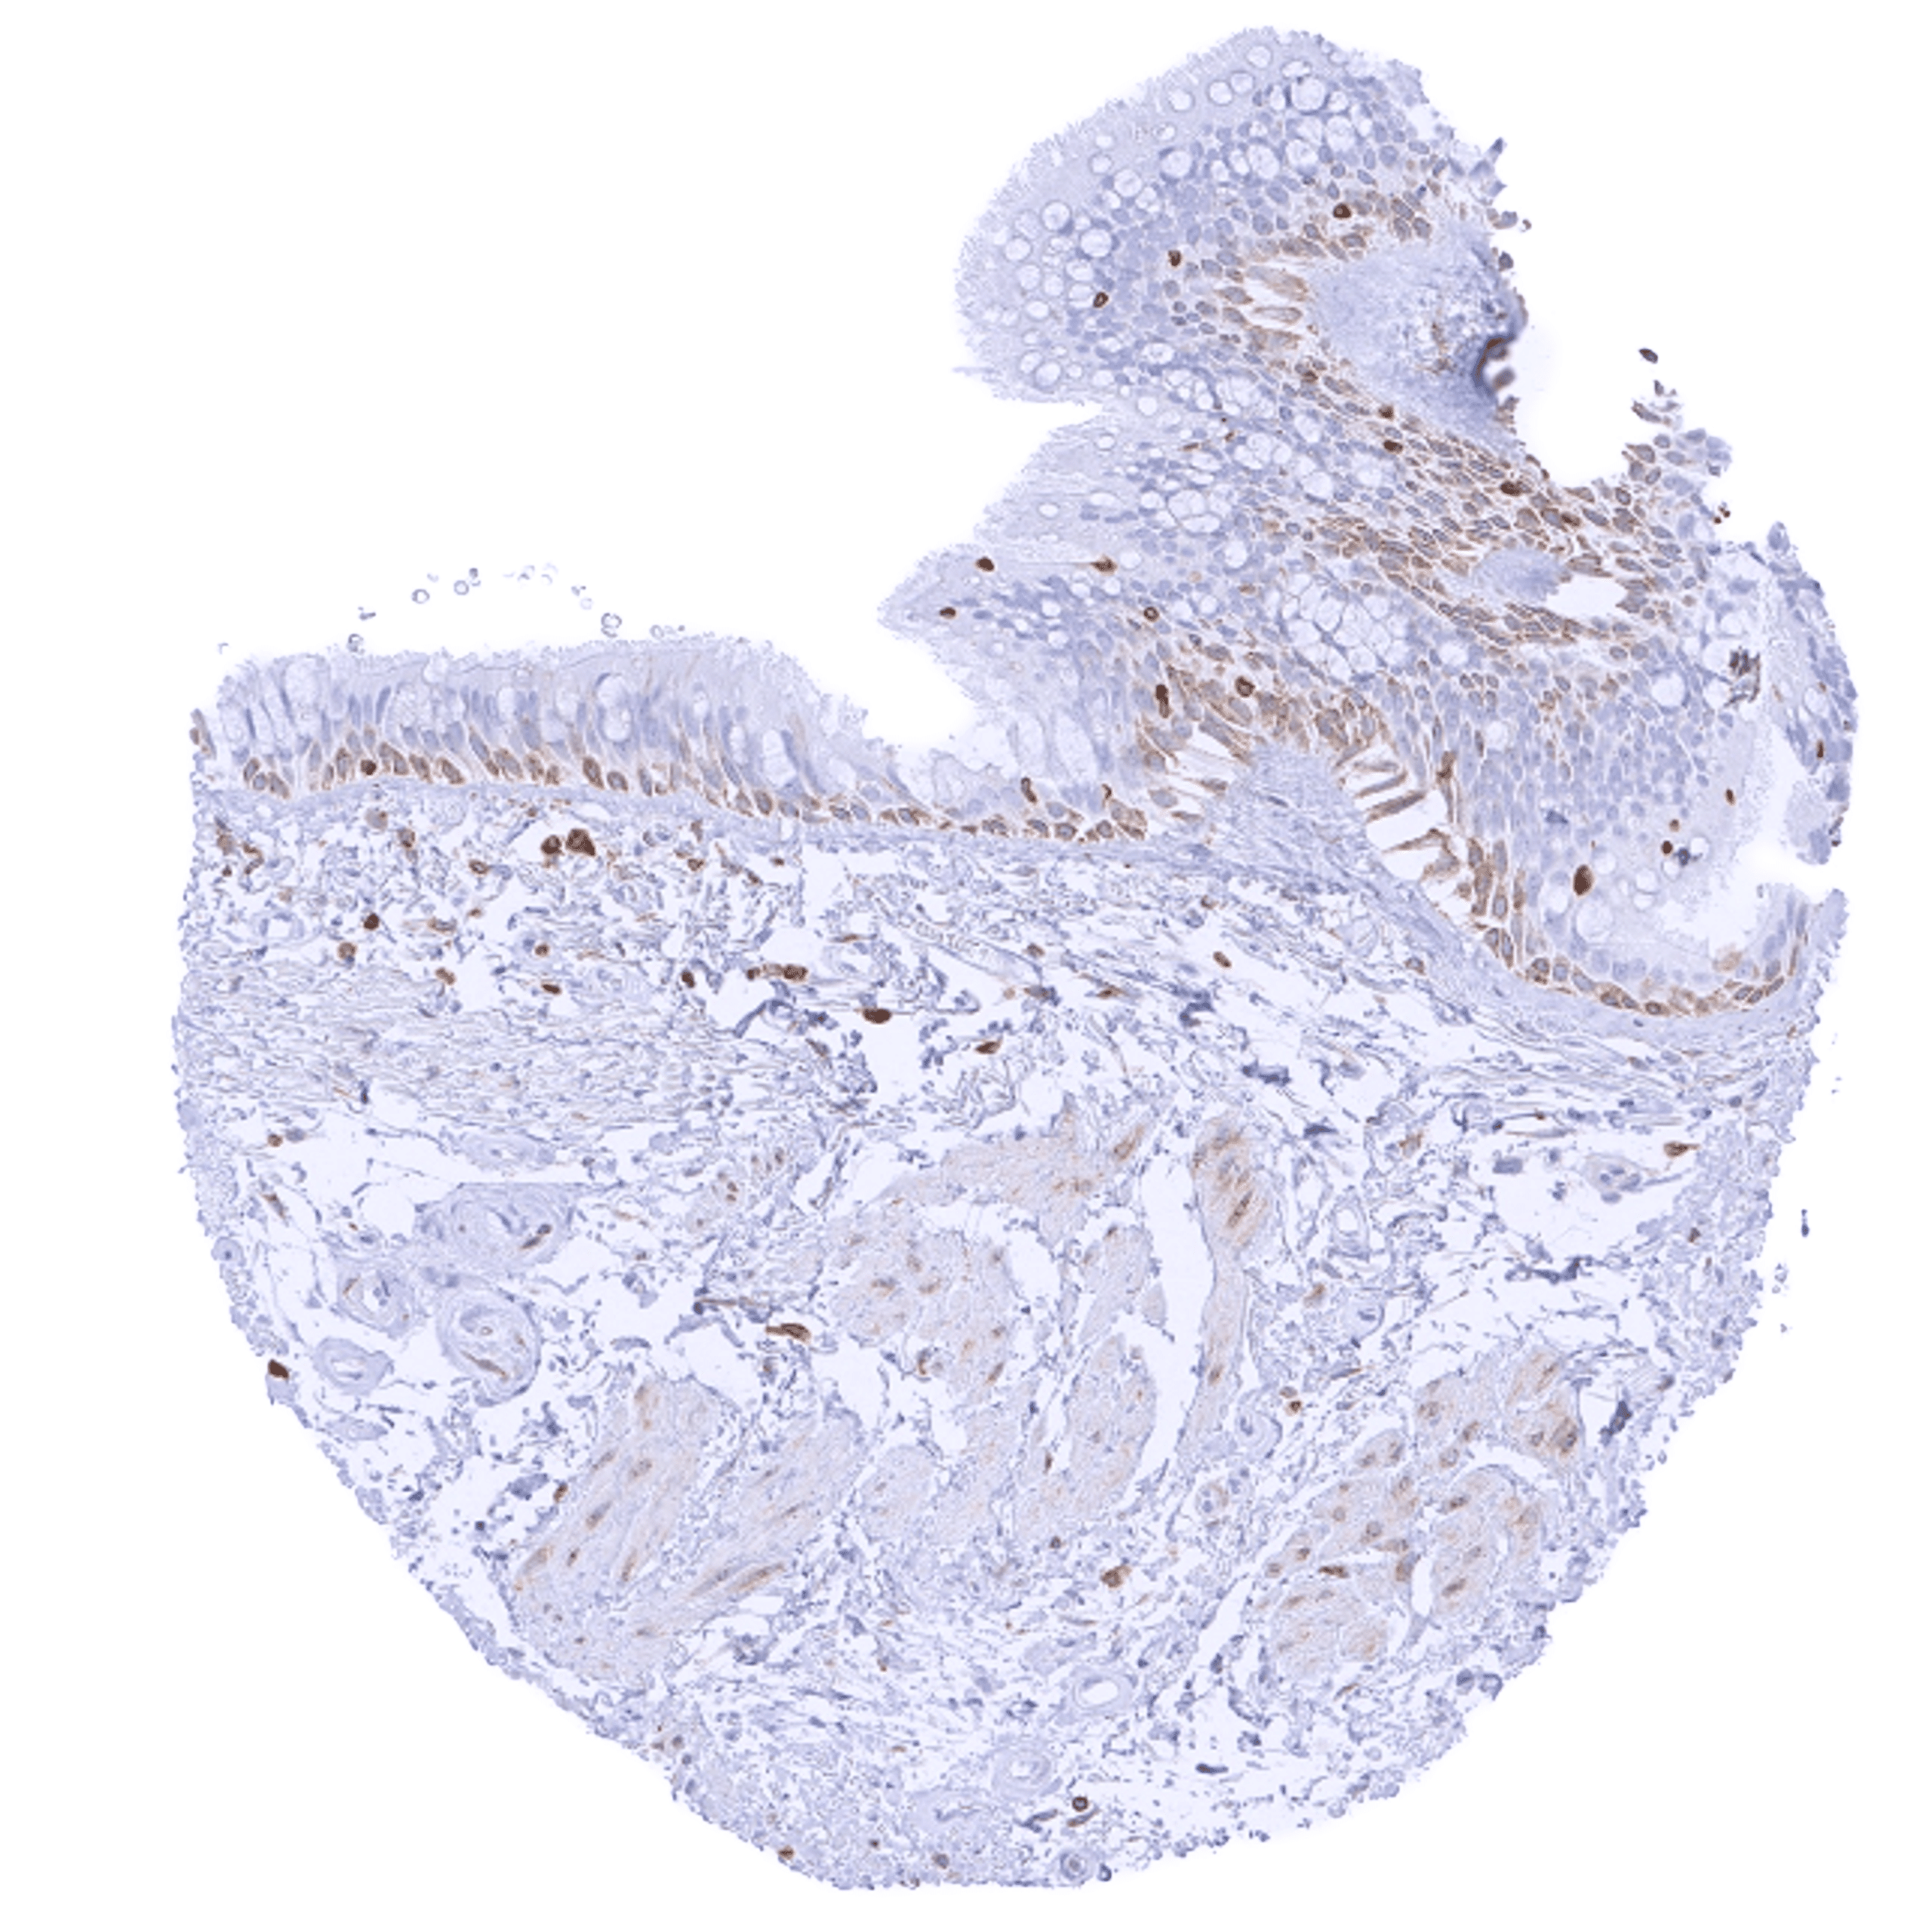

Bcl-2 expression of variable intensity can occur in all types of cancer. It is particularly common in follicular lymphoma.

Comparison of antibodies: True expression of bcl-2 in all cell types with documented bcl-2 immunostaining by MSVA-402M is validated by identical staining patterns obtained by a second, independent commercially available bcl-2 antibody, termed “validation antibody” for all analyzed tissues.